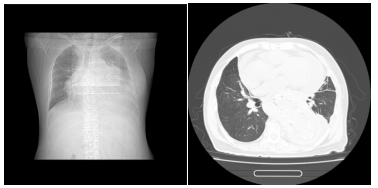

▲一位长期透析不充分的女性患者

也就是我们常说的“围透析期”,通常发生在刚开始透析,或者透析不充分的患者身上透析不充分,我们图中第二例患者就是一位未及时开始透析的终末期透析患者。如果透析次数不够、时间不足,毒素清除得不够理想,依然会持续刺激心包。